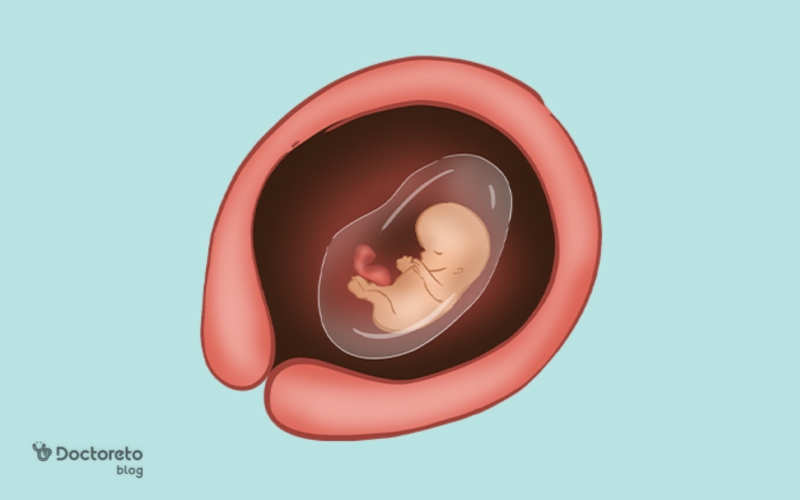

در هفته سیزدهم بارداری بیشتر اندامهای جنین تشکیل و بیشتر از قبل شبیه به نوزاد انسان شده است اما هنوز در حال تکامل است. برخی علائم اولیه بارداری کاهش پیدا میکنند و علائم جدیدی ظاهر میشوند. در این زمان جنین شروع به حرکتهای نرم در رحم میکند هرچند مادر هنوز آنها را احساس نمیکند. همچنین صورت جنین واضحتر میشود و اندامهای او، به خصوص استخوانها و اندامهای تناسلی، در حال تکامل هستند. اگر در هفته ۱۳ بارداری هستید یا بهزودی وارد این مرحله از بارداری میشوید، در این مطلب از دکترتو همراه ما باشید. در ادامه رشد جنین و تغییرات بدن مادر در این هفته را توضیح میدهیم.

جنین در هفته سیزدهم بارداری تقریبا ۷ تا ۸ سانتیمتر است. میتواند در رحم حرکت کند و حتی انگشت خود را بمکد. در این هفته تغییرات زیر ایجاد میشود:

جنین در هفته سیزدهم کجای شکم قرار دارد؟

جنین در هفته سیزدهم هنوز در لگن قرار دارد اما رحم شروع به خروج از لگن میکند. موقعیت دقیق بستگی به آناتومی مادر دارد، اما معمولا زیر ناف است. با رشد، به سمت بالا حرکت میکند. اگر احساس حرکت جنین را ندارید، طبیعی است زیرا جنین کوچک است. سونوگرافی موقعیت دقیق را نشان میدهد.